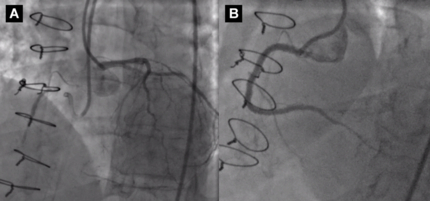

Due to concern of CTO being a sign of rapidly progressing CAV, it was decided to undergo revascularization of the RCA. Antegrade approach was performed with guidance from contralateral injections. Three overlapping drug-eluting stents were deployed proximally-distally using intravascular ultrasound guidance. Surveillance angiography nine months later showed patent RCA stents with no significant disease otherwise. Eighteen months later, angiography demonstrated CTO of the mid LAD and patent RCA stents with mild in-stent restenosis in the most distal RCA stent. The patient remained asymptomatic.